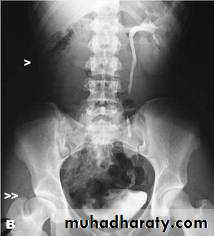

Retrocaval ureter :

The middle third of right ureter curve medially behind the IVC , then laterally to regain it’s normal position , this lead to obstruction of upper third of ureter.